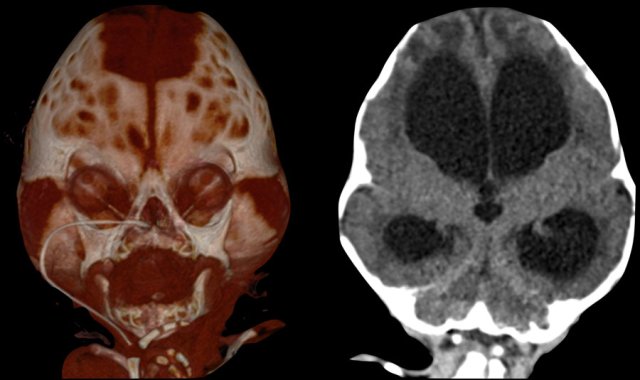

Three-month-old with Pfeiffer syndrome.

There is a bicoronal synostosis with enlarged anterior and mastoid fontanels.

Temporal bulging give rise to a trilobate appearance, also called ‘clover leaf deformity’.

Note the ventriculomegaly with periventricular edema.